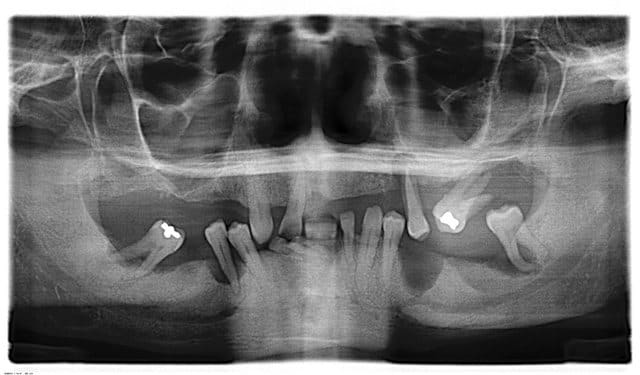

Rien d'effrayant mais plutôt inhabituel : furc distal de 36